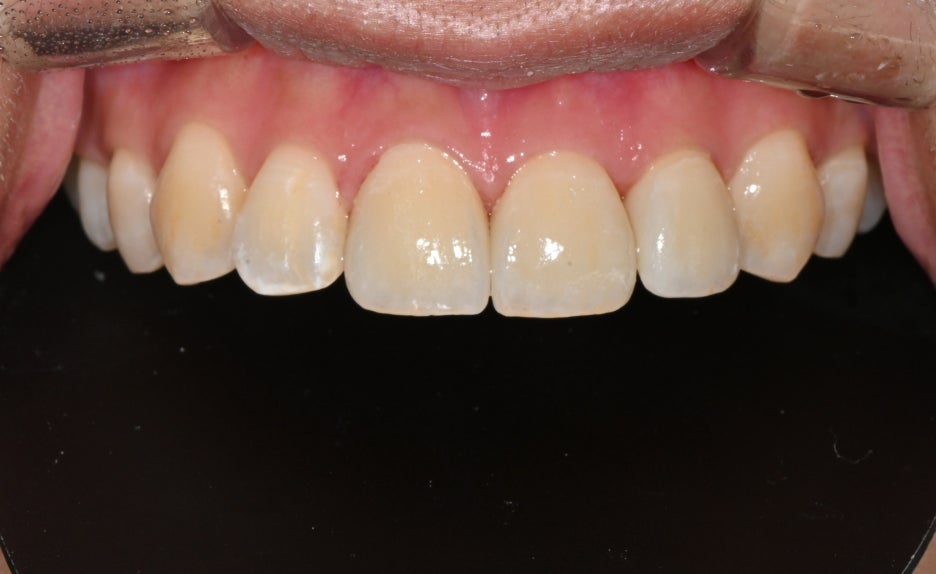

치료 전 후 사진

치료전, 치료후 사진

치료 후 환자분은

“앞니가 다시 가지런해져서 웃을 때

자신감이 생겼다”

며 만족감을 표현하셨습니다.

또한 주변 지인들이 자연스럽다고 말해주어

더욱 안심하셨습니다.